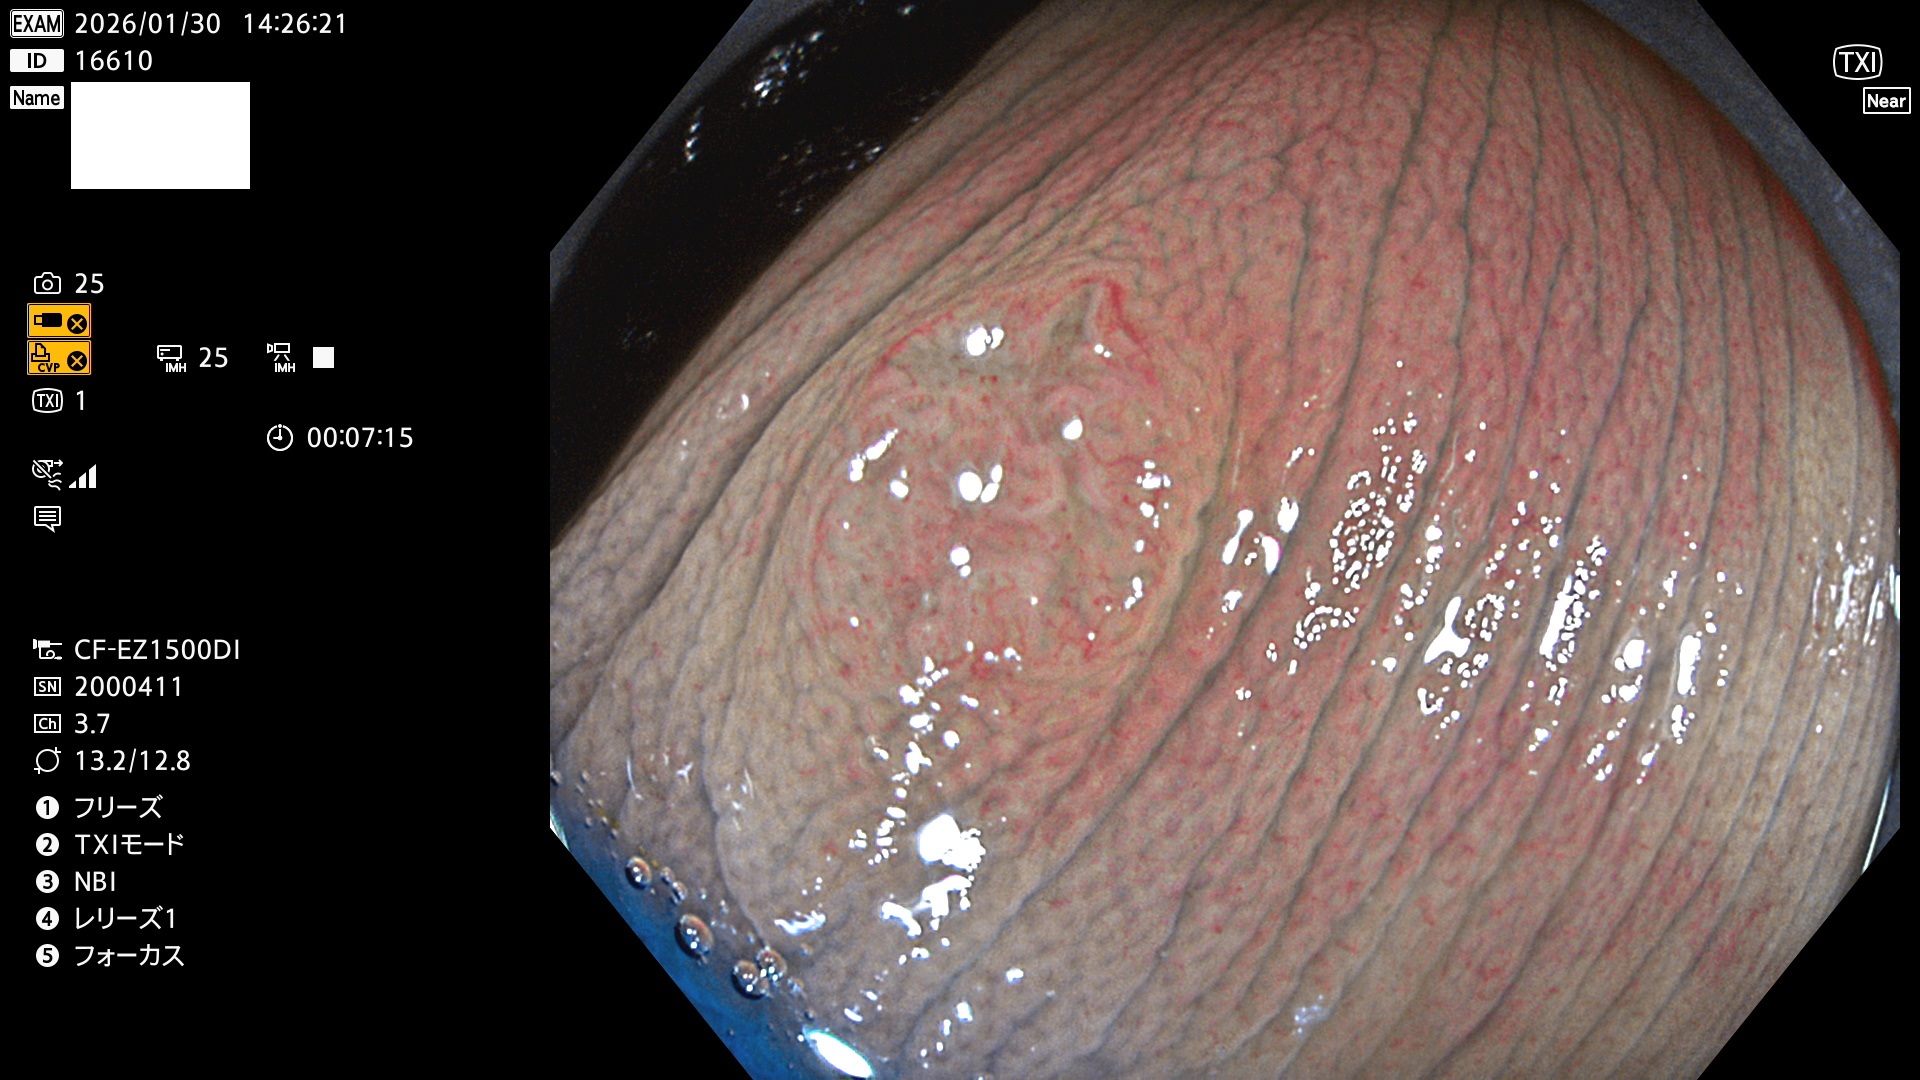

完全に平坦な物をUb、陥凹している物をUcと呼びます。Ubは認識が困難で、Ucはびらん(炎症)と紛らわしいために見落とされやすく、「内視鏡後・大腸癌」の原因になります。

毎週の検査(木・金・土・日)に発見されたUbとUc型・腺腫を、その週の日曜の夜にUPし1週間、提示します。

2026年1月29日〜2月1日の4日間(40件)10個 (Uc_ADR=10個/40人=25%)